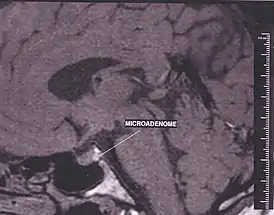

Магнитно-резонансная томография

МРТ является основным методом визуализации аденом гипофиза. У МРТ с КУ чувствительность достигает 90%. Постконтрастные изображения и особенно изображения после динамического КУ являются неотъемлемой частью протокола МР-исследования гипофиза и значительно повышают диагностическую точность. Однако иногда морфологические изменения могут быть видны и на бесконстрастных изображениях. К ним относятся изменение железы со стороны аденомы, истончение и ремоделирование нижней стенки турецкого седла, а также отклонение воронки гипофиза от аденомы [3].

- на Т1 аденомы обычно изоинтенсивны по отношению к гипофизу;

- Т1-КУ:

- на динамических последовательностях - округлая область сниженного усиления по сравнению с остальной частью железы;

- на отсроченных изображениях картина варьирует от гипоусиления (наиболее распространенный вариант) до изоинтенсивности по сравнению с остальной частью железы, до гиперинтенсивности.

- Т2 – картина различная, однако в общем – небольшая гиперинтенсивность.

Очень важно помнить следующий факт при МР-исследовании гипофиза: достаточно распространены небольшие инциденталомы гипофиза, причем примерно в 2-30% случаев при аутопсии выявляются небольшие бессимптомные микроаденомы.